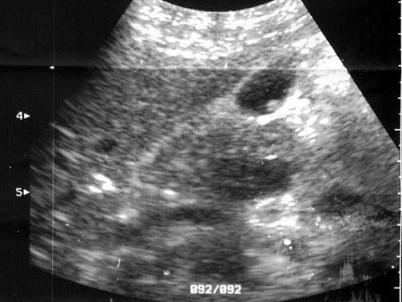

患者女27岁,体检B超检查如图所示,根据超声声像图,诊断为?(?)A.胆囊息肉B.胆囊结石C.胆囊腺瘤D.胆囊癌E.胆囊蛔虫

问题 患者女27岁,体检B超检查如图所示,根据超声声像图,诊断为?(?)

选项 A.胆囊息肉 B.胆囊结石 C.胆囊腺瘤 D.胆囊癌 E.胆囊蛔虫

答案 A